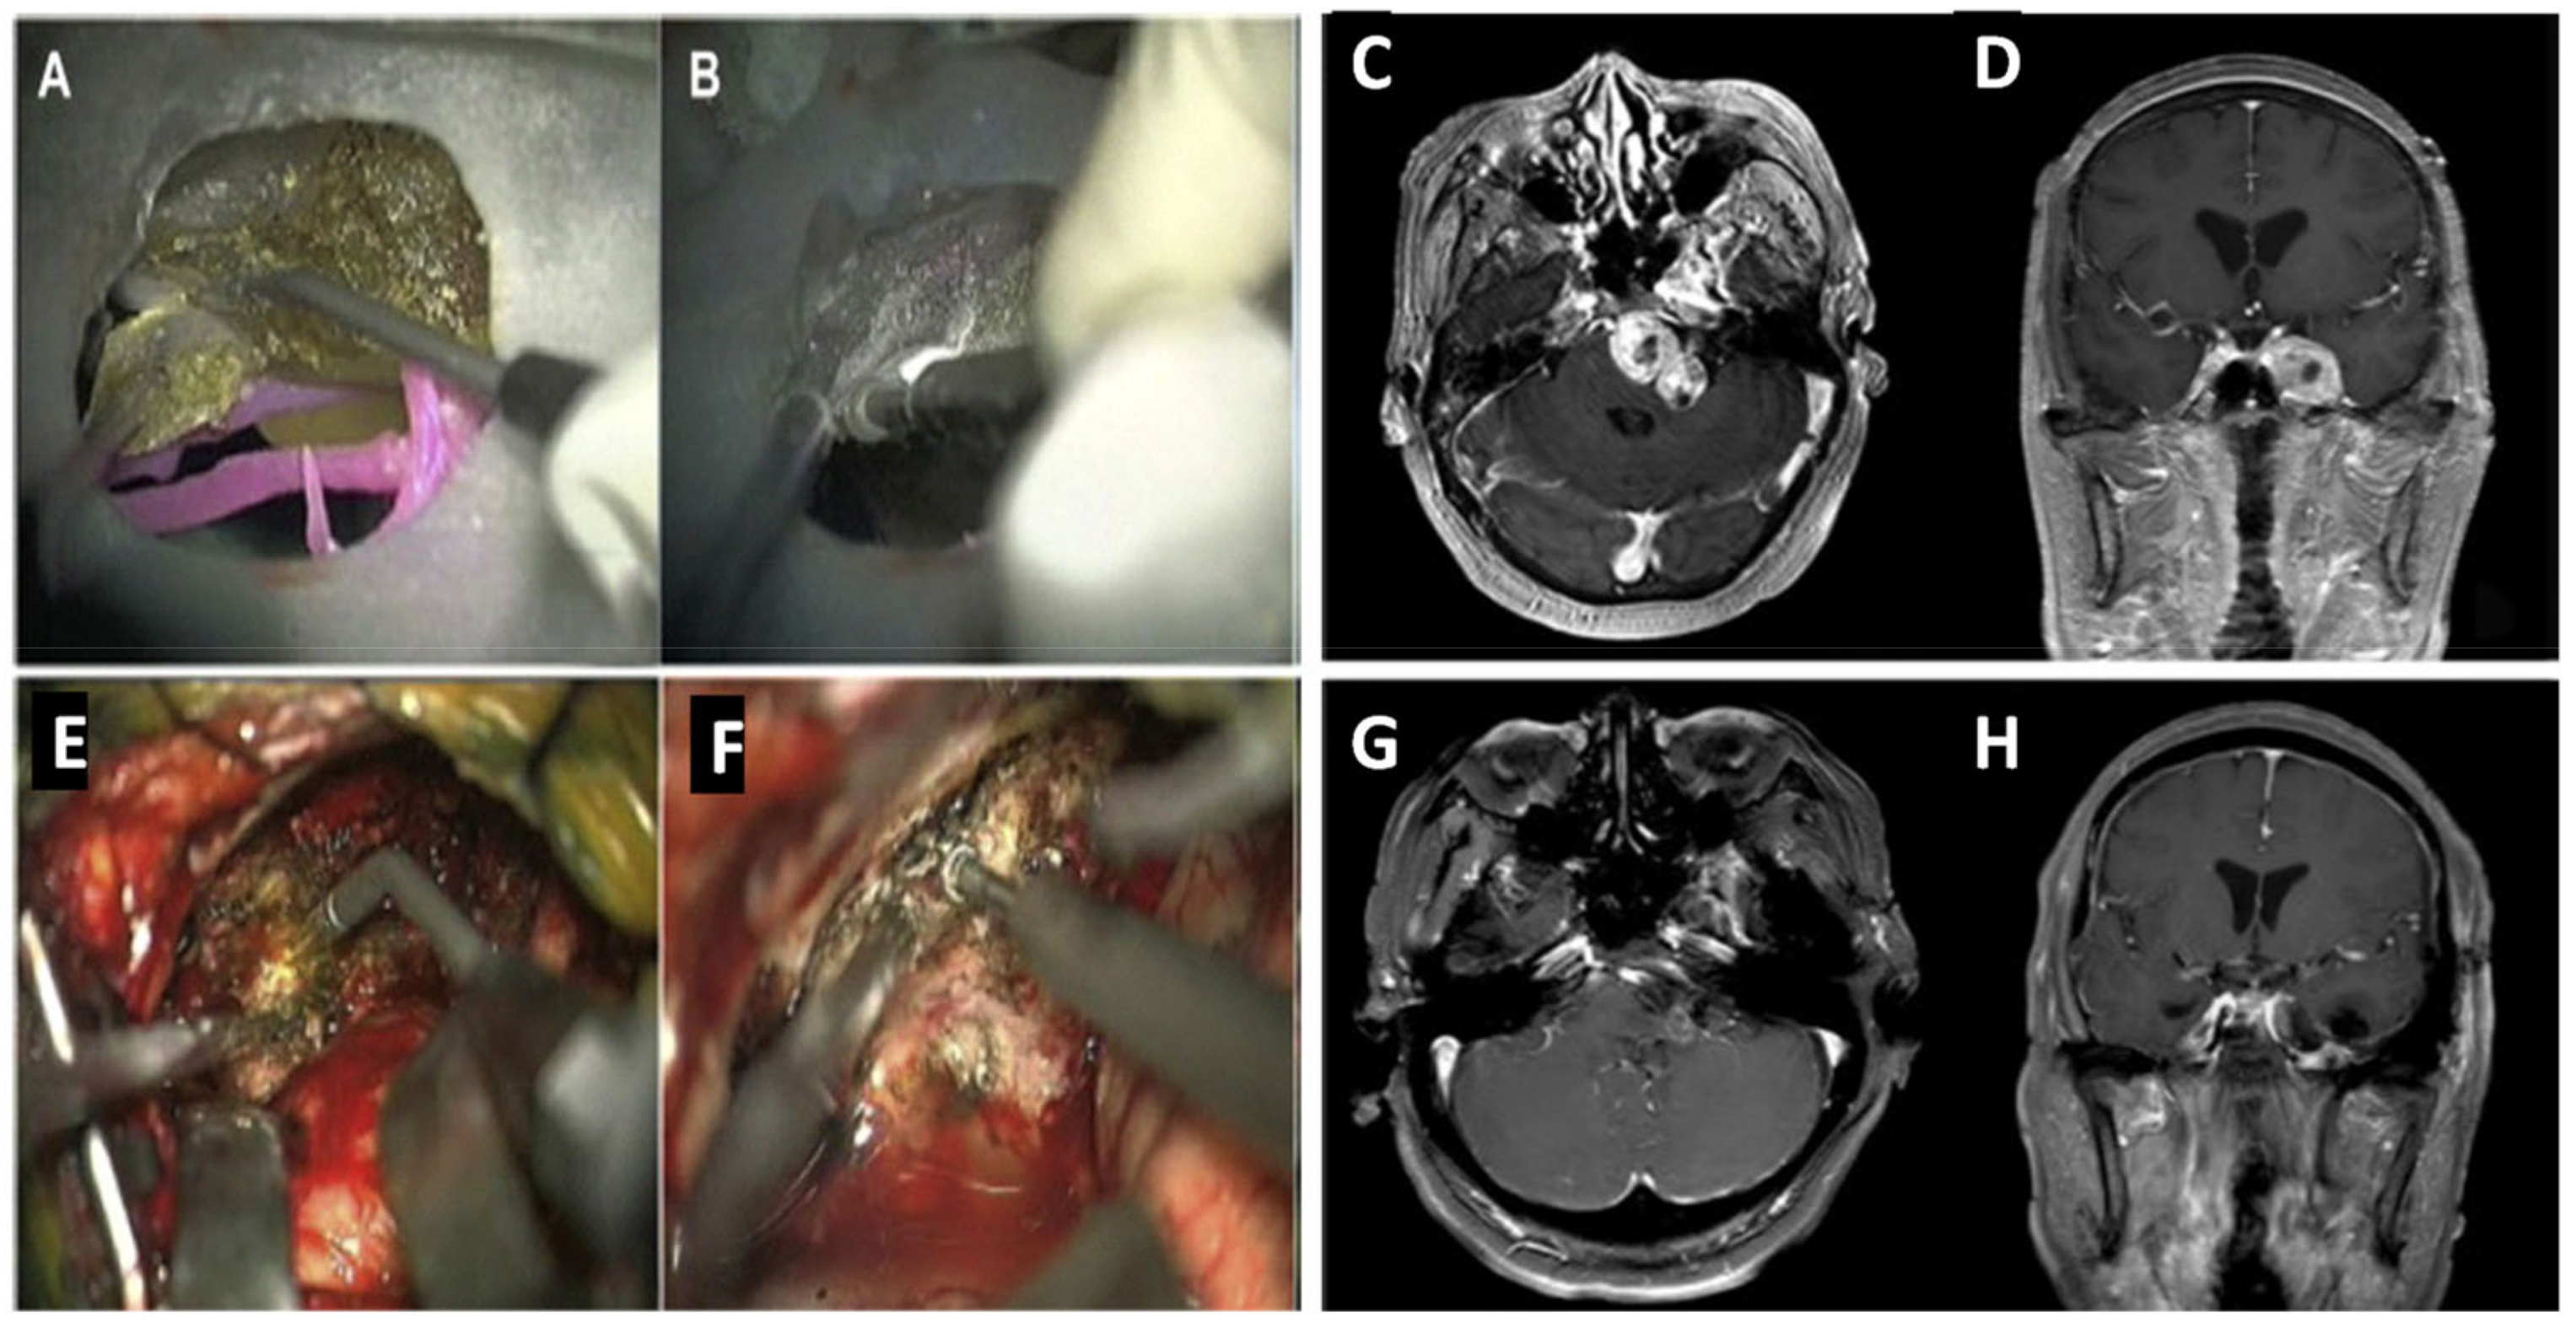

- Lan, Q.; Zhu, Q.; Xu, L.; Xu, T. Alication of 3D-printed craniocerebral model in simulated surgery for complex intracranial lesions. World Neurosurg. 2020, 134, e761–e770. [Google Scholar] [CrossRef] [PubMed]